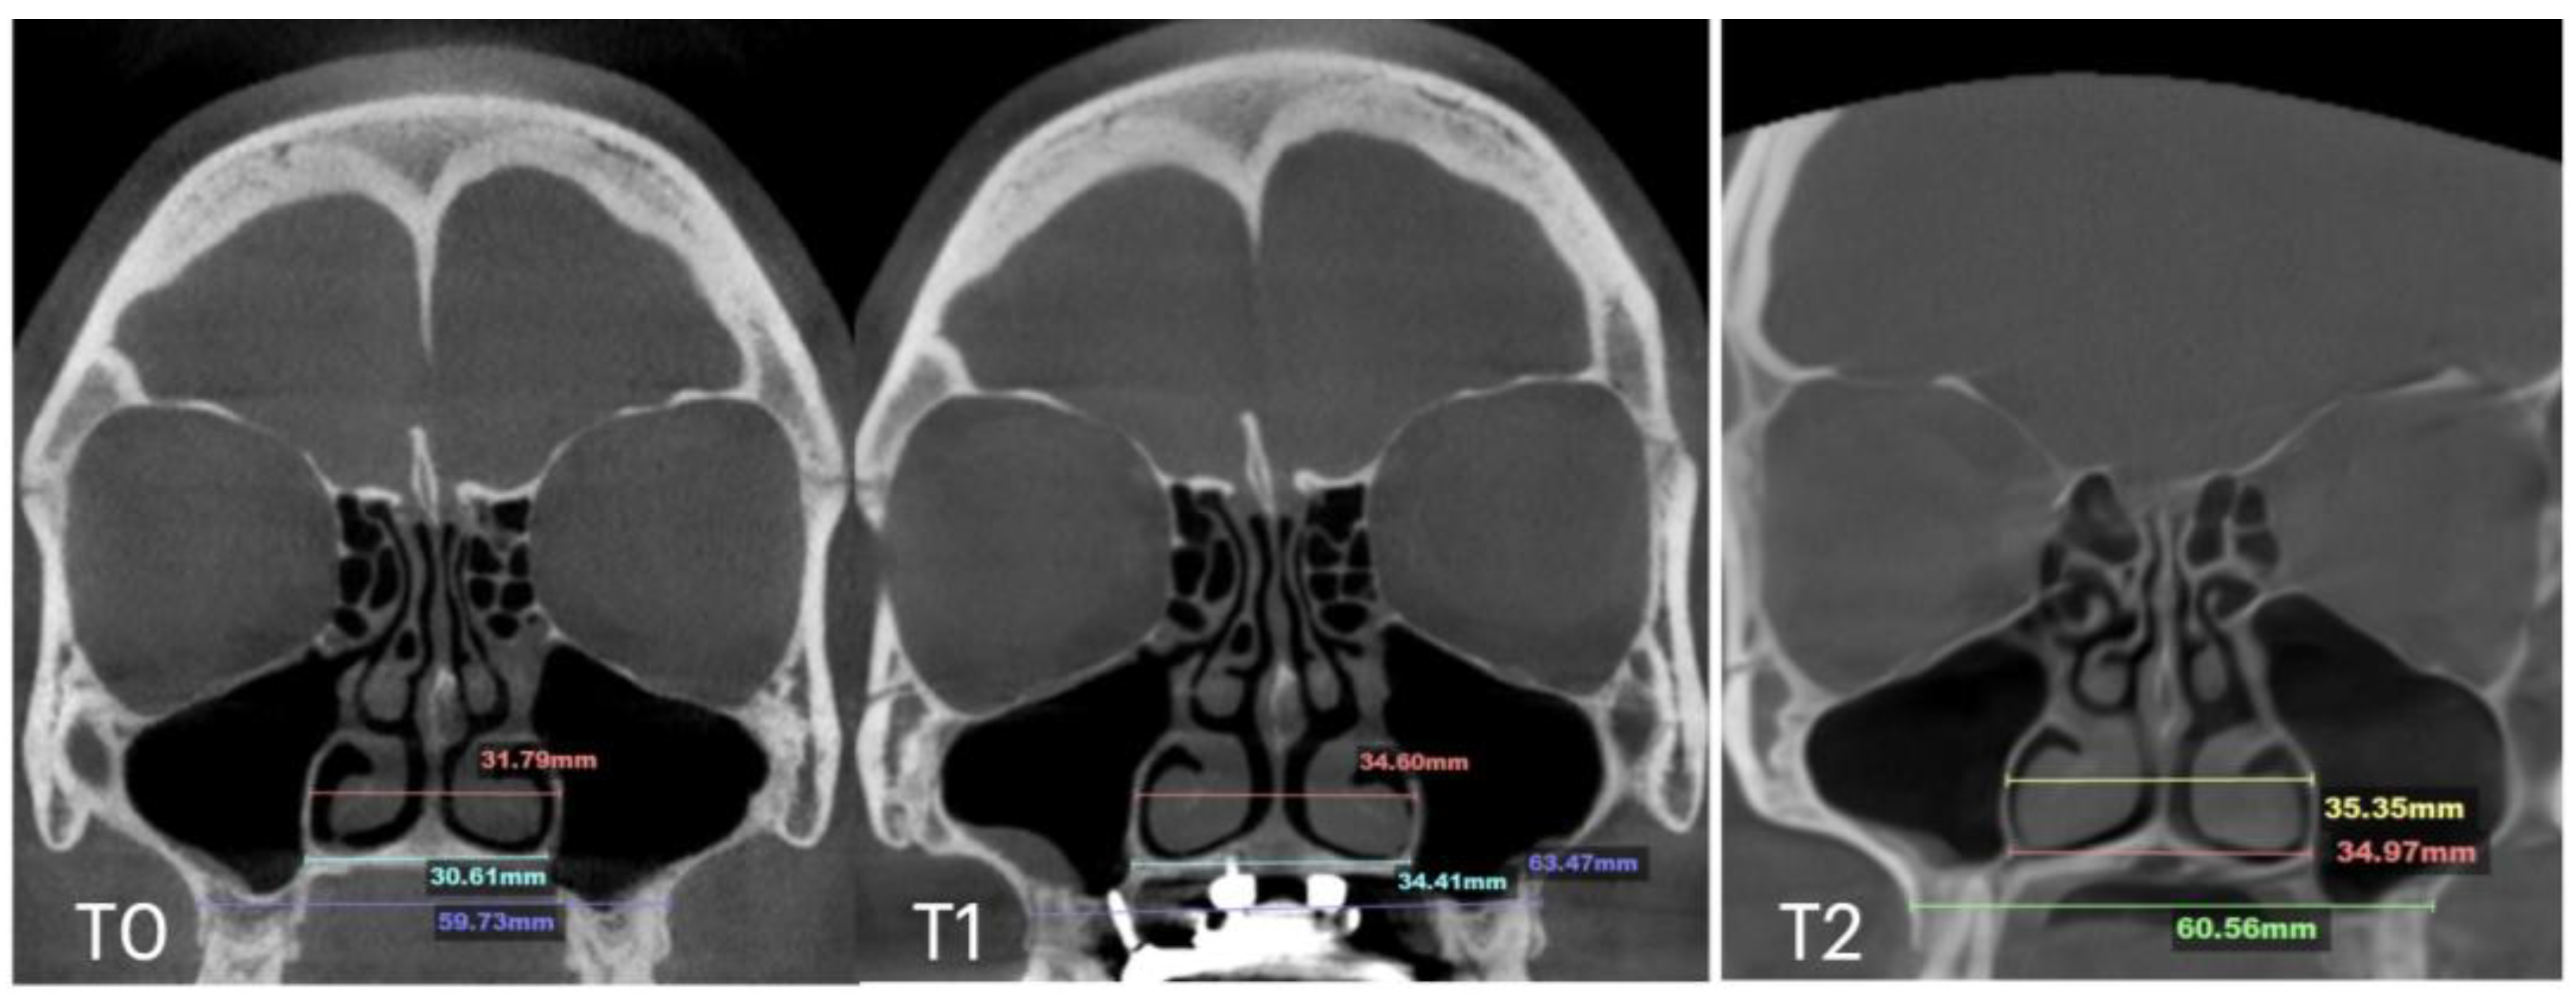

| Nasal Base Width, mm | Maxillary Base Width, mm | Lateral Nasal Width, mm | Inter-Pterygoid Distance, mm | Midpalatal Suture Separation, mm | |||||||||

|---|---|---|---|---|---|---|---|---|---|---|---|---|---|

| T0 | T1 | T2 | T0 | T1 | T2 | T0 | T1 | T2 | T0 | T1 | T2 | T1 | |

| Case B | 30.61 | 34.41 | 34.97 | 59.73 | 63.47 | 60.56 | 31.79 | 34.6 | 35.35 | 29.18 | 31.38 | 34.59 | 5.7 |